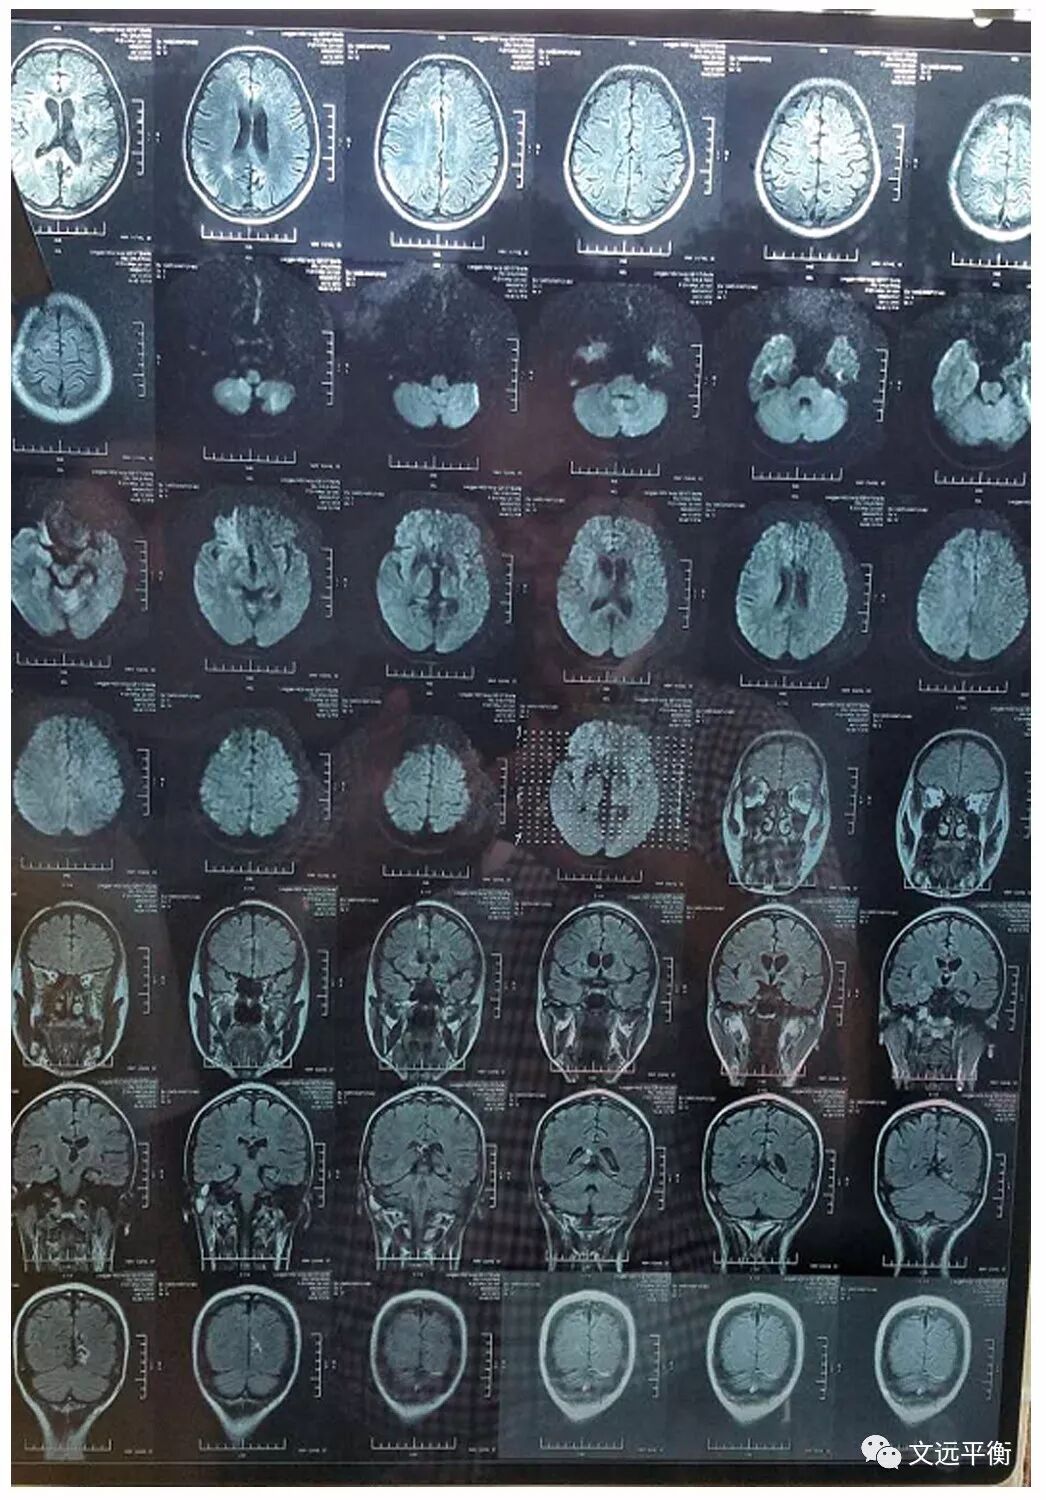

影像资料对比:图一、二。MRI平扫+增强+灌注扫描(2013.2.25宣武医院)报告提示:脑内多发异常信号,梗死伴渗血?血管炎?右侧乳突炎)

图四、五:复查颅脑MRI(2016.7.13龙岩市第二医院)提示:右侧基底节区,左枕叶.右侧额叶多发软化灶并周围胶纸增生,右侧额骨术后改变?